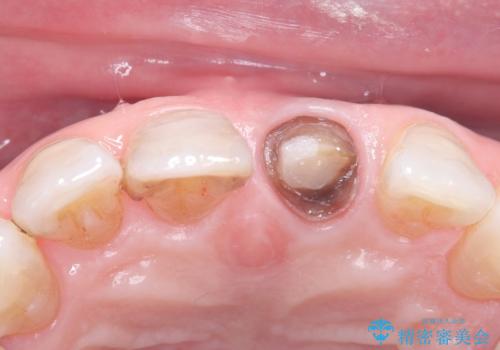

- 歯髄が死んで変色していた歯に対して、根管治療とオールセラミッククラウンでの修復を行いました。まず、根管治療で内部の感染を除去し、歯の強度を高めるためにファイバーコアを装着しました。その後、審美性と耐久性を考慮し、オールセラミッククラウンで覆うことで、自然な歯の色合いに近い美しい仕上がりを実現しました。

歯髄が死んだ歯は通常の健康な歯に比べて透過性が低く、特有の暗い色調を帯びる傾向にあります。変色は時間とともに進行し、薄い茶色や灰色、黄色がかった色合いになることが多いです。このような変色は、審美的な面で気になる場合が多く、オールセラミッククラウンなどでの修復が行われることも一般的です。